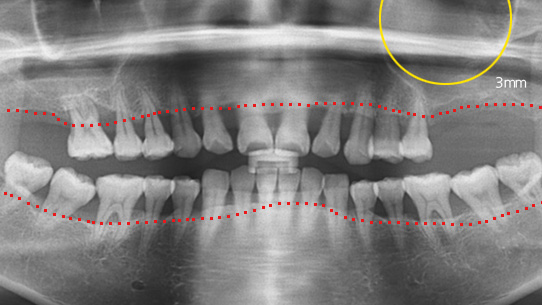

타 치과 에서 6개 치아를 발치하고 12개 임플란트 식립을 진단받고 내원. 고운미소에서 치주치료를 통하여 치아를 보존 시키고 6개의 임플란트 식립한케이스

잇몸뼈가 녹아내려 다른 병원에서 임플란트 12개 진단을 받고 내원, 고운미소에서 치주치료를 시행한 결과 전치부 잇몸이 개선되어 발치 하지 않고 크라운으로 수복하였고, 어금니에 6개의 임플란트를 식립하였습니다.